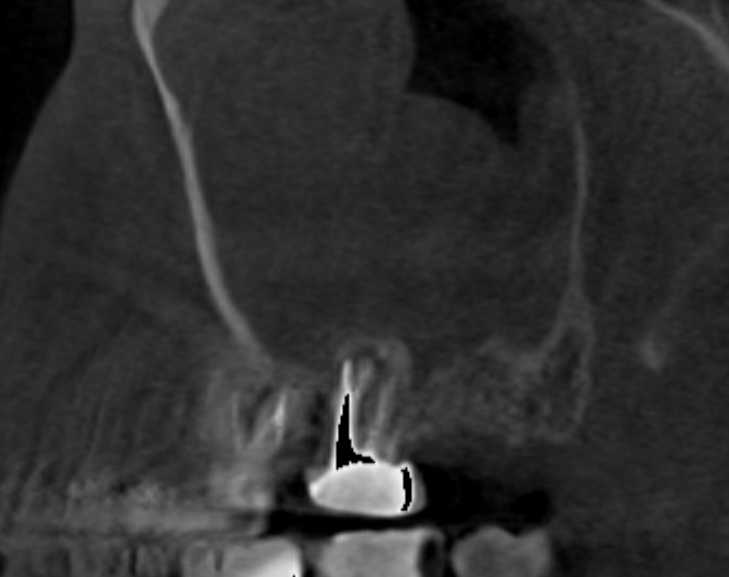

Добрый вечер. История очень длинная...  пол года болею именно клинически, хотя процесс как оказалось с 2020 года где то, тогда когда чувствовал себя здоров полностью, из-за причинных зубов.

26 зуб в марте я попросил что бы попробовали перелечить. нашли в итоге 4 канал и спустя несколько месяцев отмечается улучшение небольшой, обрастает костью, 8 удалил 1 апреля,  3 недели назад перепаковали 7, там перфорация была., долго ждал специалиста по эндодонтии, ибо для остальных даже эндодонтов он труп был, но опять же прогноз под вопросом и я это понимаю, переделал каналы и закрыл перфорацию врач известный на весь снг, фамилии писать не буду, далее было 2 гайморотомии, одна через нос, после уже экстраназальная, при второй лишь удалось вытащить мицетому с пломбировочным материалом. На 7зуб на сл  неделе попробуем временную коронку... После операции второй прошло 10 дней, но клиника вот вся эта полугодичная еще сохраняется.

Скажите, есть ли шанс попробовать подождать еще, касательно 6 и 7 зуба, или как быть ?

image.png.12405cfc51414f93b6b5a12ce7098a18.pngimage.png.f7a79906207cc5c9c8bcd95d65b7bb29.png